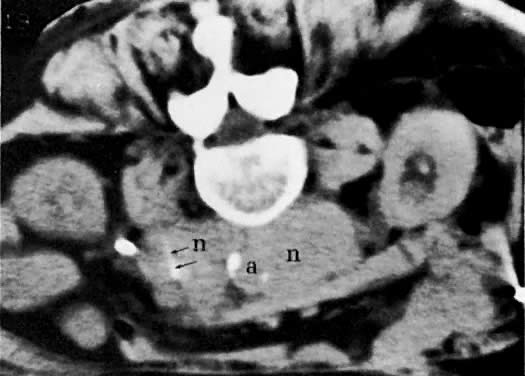

Fig. 48. Massive para-aortic metastases from endometrial carcinoma with bony invasion. A. CT scan of the midabdomen shows confluent, massively enlarged para-aortic lymph nodes ( n) encircling the aorta ( a) and displacing it anteriorly. Note the destructive changes in the vertebral body ( arrow ). B. Cone-down view of the vertebral body shows massive bony destruction ( arrows) caused by para-aortic lymphadenopathy.

The diagnosis of lymph node metastases by CT depends predominantly on the increase in their size, but occasionally there is also a change in density (see Fig. 45B and Fig. 45C). Normal lymph nodes measure less than 1 cm in diameter. An isolated para-aortic or iliac lymph node measuring 1 to 1.5 cm should be considered suspicious (see Fig. 45C), and a clustering of small lymph nodes should be considered abnormal (see Fig. 38C). Lymph nodes larger than 1.5 cm in diameter also should be considered abnormal (see Fig. 45B).123 Metastatic lymphadenopathy is occasionally visualized as a conglomerate group of contiguous enlarged lymph nodes similar in size to the aorta or inferior vena cava, or as a large, homogeneous mass (see Fig. 48A).124 A false-negative diagnosis by CT is caused by the technique's inability to diagnose metastases in normal-sized lymph nodes. Because metastases from cervical carcinoma often replace part of a lymph node without enlarging it, the reported false-negative rate has been as high as 40%.25 A false-positive diagnosis results from the inability of CT to differentiate enlarged nodes caused by hyperplasia from those caused by metastases. CT-guided percutaneous fine-needle aspiration biopsy of the enlarged lymph nodes may be required (Fig. 49). Extension of tumor into lymph node groups not opacified by lymphography (e.g., mesenteric lymph nodes) can also be detected by CT, and biopsy specimens of these nodes can be taken during CT scanning.